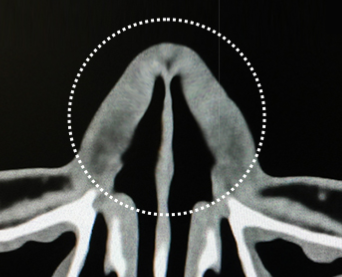

수술 전 정밀 진단

3D-CT와 비내시경

3D-CT |

BEFORE | AFTER | ||

최첨단 3D-CT를 통해 육안으로 식별이 불가능한 코의 골격과 구조 등

기능적인 문제를 정확하게 진단합니다.

비중격만곡증, 비염, 비밸브협착의 유무 등을 확인하여

기능적인 문제점을 보다 정확하게 개선할 수 있습니다.